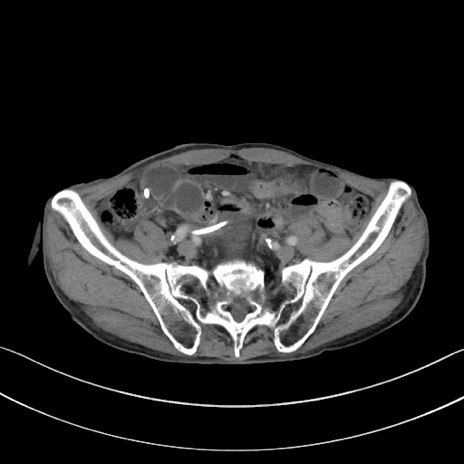

症例3(横断像)

【症例】 70歳代男性

【主訴】右鼠径部腫瘤、疼痛

【現病歴】本日朝より上記主訴あり、受診。

【既往歴】膀胱癌にて膀胱全摘、両側尿管皮膚瘻

【データ】WBC 5600、CRP 0.56